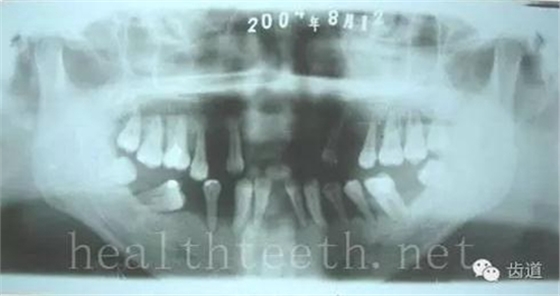

牙片顯示牙槽骨的垂直吸收

外院做的牙周固定,牙片顯示牙槽骨的水平吸收